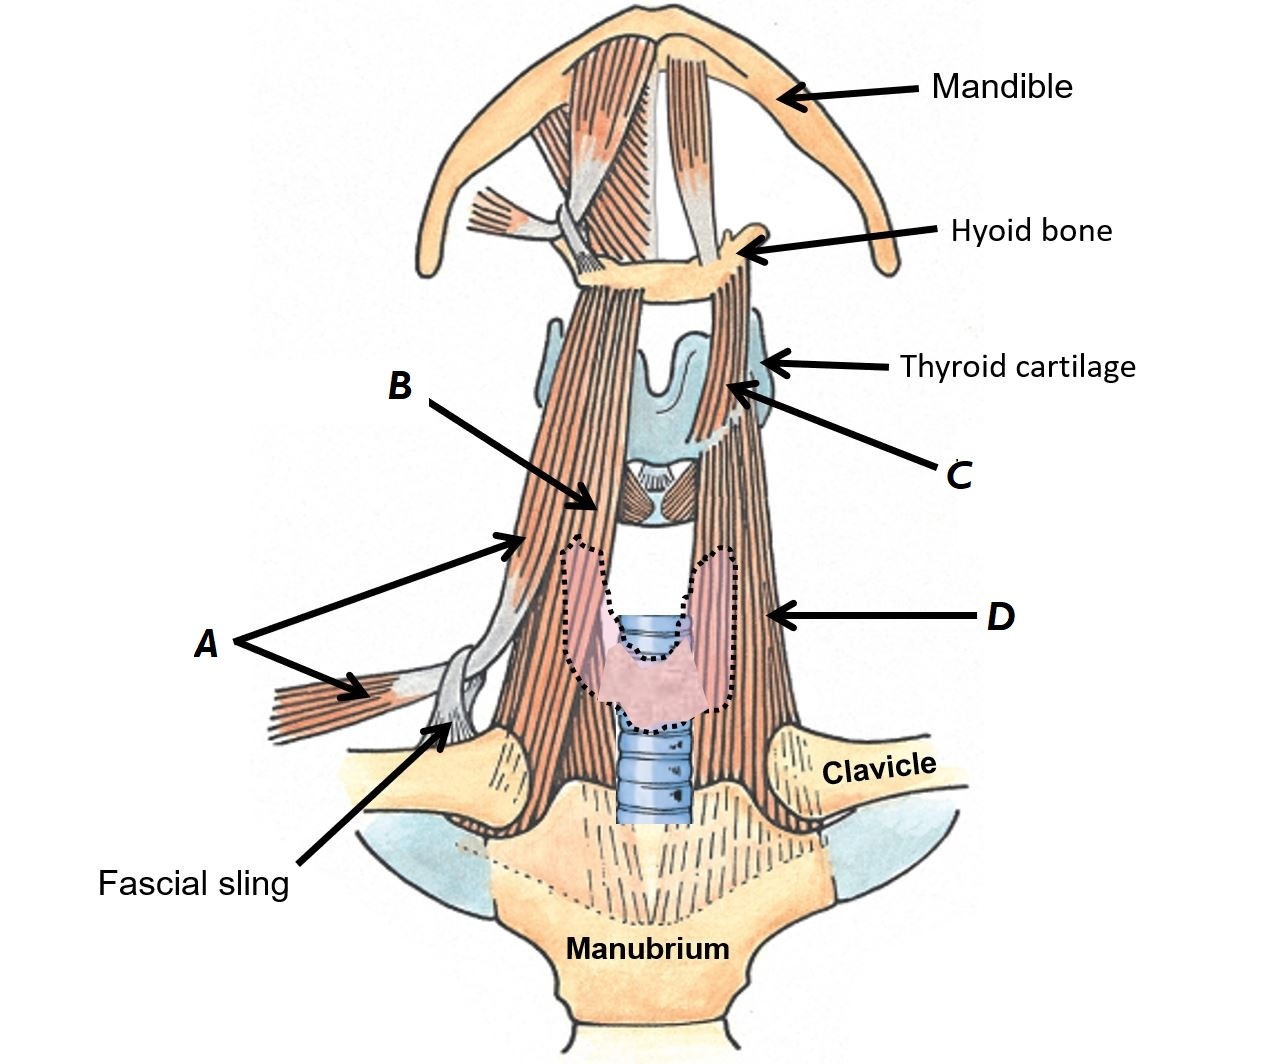

Name muscles A to D

A - Omohyoid muscle

B - Sternohyoid muscle

C - Thyrohyoid muscle

D - Sternothyroid muscle